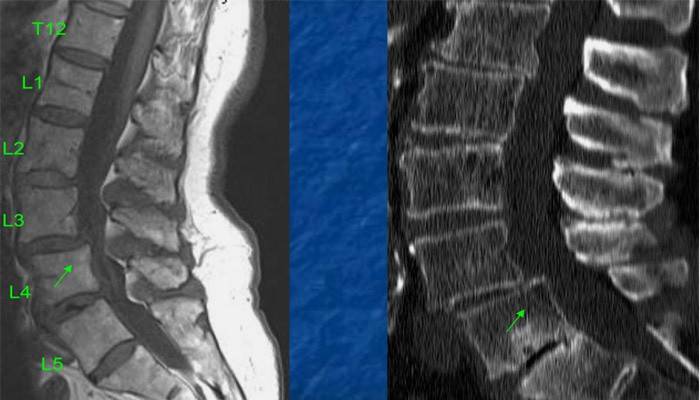

Si hay una sospecha de espondiloartrosis lumbosacra de la columna vertebral, los médicos primero determinan la ubicación y el grado de daño al sistema musculoesquelético. Para esto, se realizan manipulaciones físicas simples: presión, golpes, etc. Al finalizar el examen inicial, los médicos proceden a los principales métodos de diagnóstico. Dependiendo de las circunstancias, el paciente puede recibir una tomografía computarizada y / o una resonancia magnética. Estos estudios permiten obtener imágenes claras de las secciones de la columna de interés y establecer un diagnóstico preciso basado en ellas.